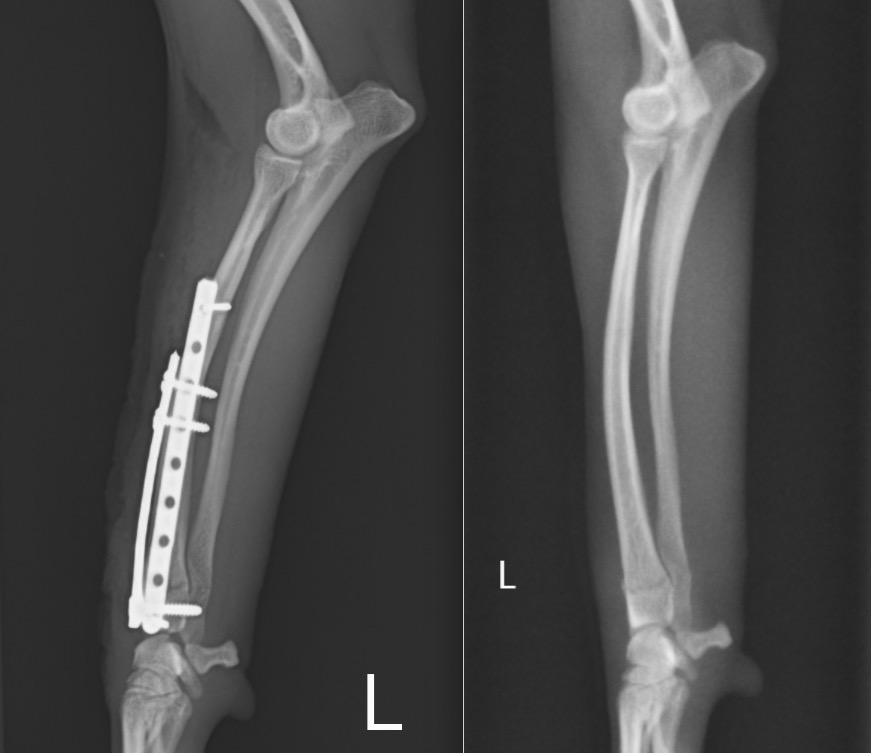

手術はダブルプレート法で行いました。

正面に1.5㎜コンディラープレート、側面に1.1mmストレートプレートを設置し、

結果的には手首の関節に近い小さい骨片にも3本のスクリューを挿入することができました。

左:術後 / 右:術前